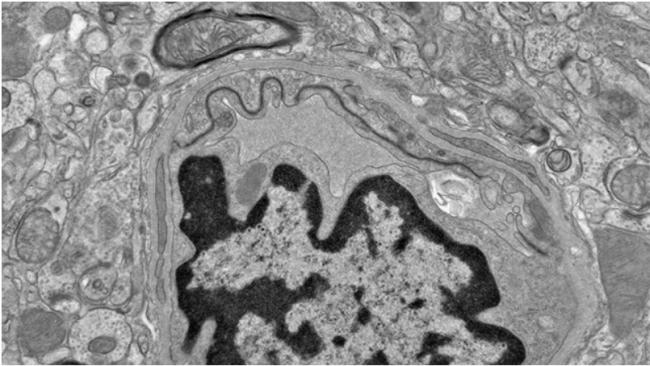

在后续实验中,研究人员利用人源脑微血管内皮细胞(构成血脑屏障的关键细胞)进行测试,结果显示DHA并未干扰修复过程。

研究团队进一步分析发现,在患有慢性创伤性脑病(CTE)的人类脑组织中,也存在类似的代谢紊乱和血管损伤现象。该疾病通常与反复头部撞击有关。